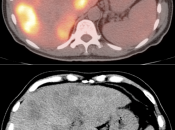

Presentation of Primary Cancer:

- Focal bowel uptake, usually with associated bowel wall thickening.

- If long-segment, think inflammation.

- If diffuse, usually normal physiologic uptake.